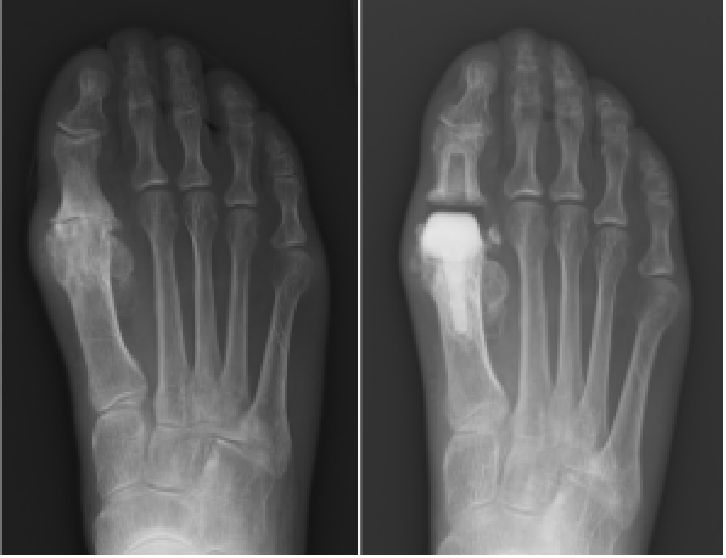

つま先の痛みと変形 外反母趾、強剛母趾、内反小趾、屈趾症、モートン病

の外科的治療:症例

保存療法では治療が見込めない患者様に対しては、人工足関節置換術、矯正骨切り術、遠位脛骨斜め骨切り術、関節固定術、血管柄付き腓骨移植、再建術などの外科的治療を提案をしております。

外科的治療:症例一覧